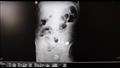

بعض الأطباء في تركيا كانوا في حيرة من أمرهم، وذلك بعد العثور على مئات العملات المعدنية والمسامير والبطاريات وشظايا الزجاج داخل معدة رجل، وفقا لصحيفة metro البريطانية.

برهان دمير من مدينة إبيكيولو بتركيا، نقل شقيقه الأصغر إلى المستشفى بعد أن اشتكى من آلام في البطن، ولكن عندما أجرى الأطباء جراحة المنظار الداخلي باستخدام الموجات فوق الصوتية والأشعة السينية، اندهشوا من اكتشاف 233 عنصرًا في معدة الرجل البالغ من العمر 35 عامًا.

وشملت هذه العملات عملات ليرة واحدة وبطاريات ومغناطيس ومسامير وقطع زجاج، وأحجار ومسامير.

وأزال الجراحون هذه العناصر من معدة المريض، إذ قال جراح يُدعى الدكتور بينيسي: "أثناء الجراحة، رأينا أن واحدًا أو اثنين من المسامير قد مرت عبر جدار المعدة، رأينا أن هناك قطعتين معدنتين وحجرين بأحجام مختلفة في الأمعاء الغليظة".

وأضاف: "كما وجدنا أن هناك بطاريات ومغناطيس ومسامير وعملات وقطع زجاج ومسامير، قمنا بتنظيف بطن الشخص تمامًا، إنه ليس أمرا معتادا أن نراه عند البالغين، في الغالب يحدث ذلك في مرحلة الطفولة، حيث ابتلاع أجسام غريبة عن غير قصد".